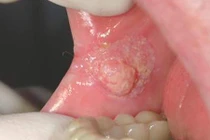

| Số bệnh nhân ung thư khoang miệng đang ở mức đáng báo động trên toàn thế giới. |

Trong 20 năm qua, các chẩn đoán ung thư miệng đã tăng vọt 135% ở Anh. Chỉ riêng năm 2018, bảy người chết mỗi ngày vì căn bệnh này trong tổng số 8.337 bệnh nhân ở Anh và Bắc Ireland.

Tỷ lệ này tại Mỹ cũng tương đương khi theo số liệu thống kê của tổ chức Ung thư miệng (OHF), có khoảng 54.000 người Mỹ được chẩn đoán mắc bệnh ung thư miệng hoặc vòm họng (bao gồm thanh quản) mỗi năm, với ít nhất một bệnh nhân tử vong mỗi giờ/ngày, gây ra khoảng 13.500 ca tử vong mỗi năm.

Ở Mỹ, tỷ lệ sống sót sau 5 năm đối với các căn bệnh ung thư thuộc khoang miệng là khoảng 57%. Nhưng những người thoát khỏi lưỡi hái của căn bệnh này có thể phải sống phần còn lại của cuộc đời mà không có lưỡi hoặc hàm.

Carter gọi bệnh ung thư khoang miệng là một căn bệnh tàn khốc. “Nó làm méo mó cách phát âm, khiến việc ăn uống trở nên khó khăn hơn và thường làm thay đổi ngoại hình của một con người”, ông nói.